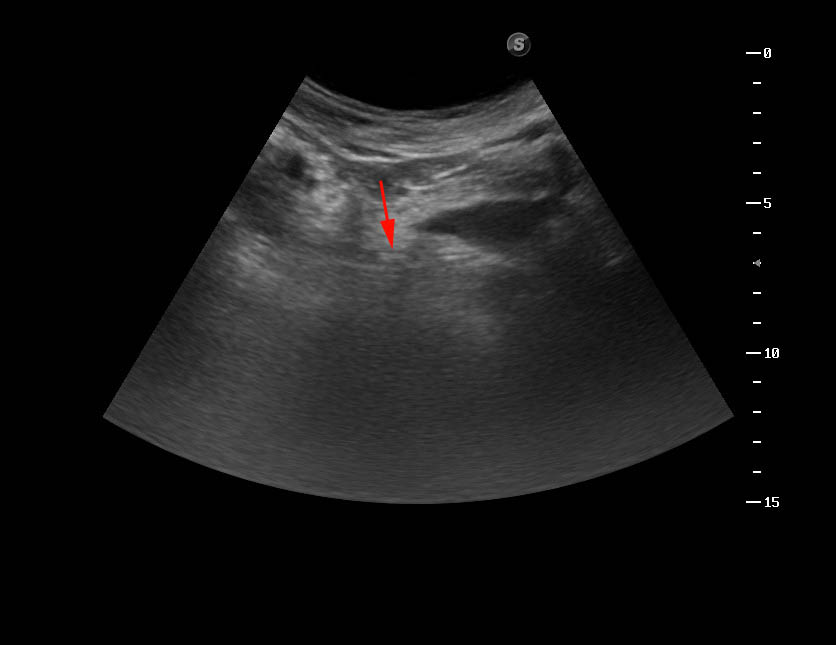

УЗИ: инспекция мочеточника. Sonographic inspection of an ureter. #3